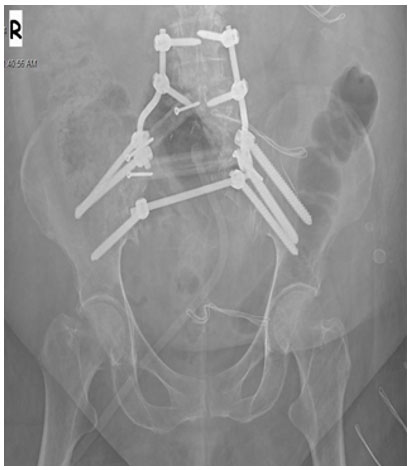

Ameliyat sonrası: Röntgende fibula ve lumbopelvik fiksasyon ile yapılan rekonstrüksiyon görülmekte